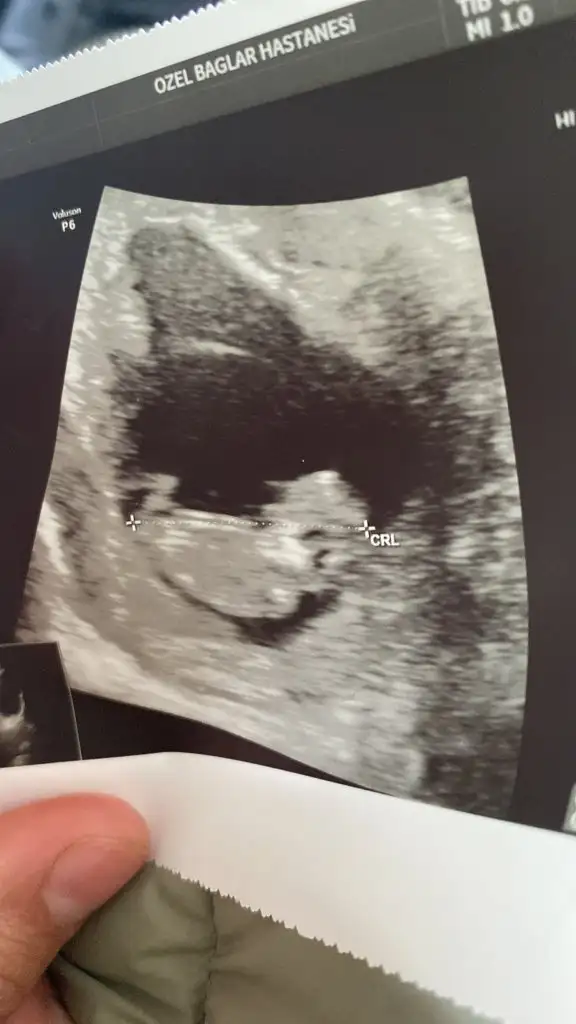

Canım bu kocaman olmuş maşallah ben 6 ile 9 hafta arası anlıyorum daha önce bakmışmıydık sana. Baktıysak o geçerli. Eski ultrason varsa at. Bebeğin yerine göre yorum yapıyorum ben.

Karın ultrasonu ise kız. Vajinal ise erkek diyorum caney